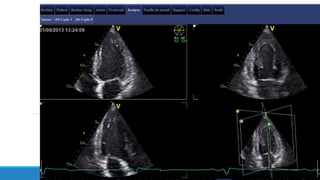

Techniques d’acquisition des images

Etape 1:

Obtenir des images de l’oreillette gauche en 4 cavités.

Etape 2:

Un traçage des contours endocardiques de l’oreillette gauche est réalisé

manuellement par l’opérateur et les contours épicardiques sont tracés

automatiquement par le logiciel, ainsi; une zone d’intérêt est crée.

Etape 3:

La paroi de l’oreillette gauche est divisée en 6 segments et le logiciel fait valider ou

non la zone de traçage réalisé pour chaque segment, une fois tous les segments sont

validés, la zone d’intérêt est approuvée et l’étude peut être réalisée.